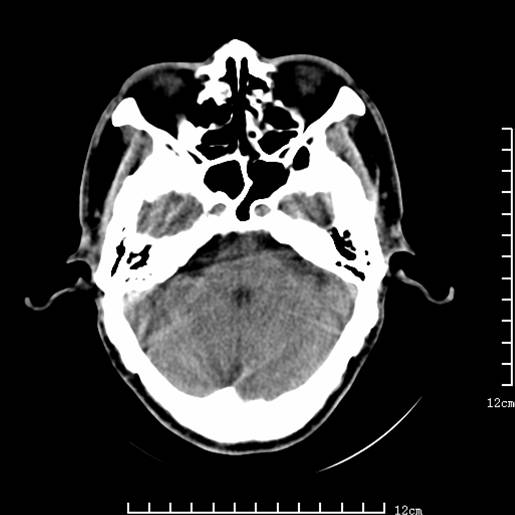

以下图像分别是3月25日凌晨及下午图像、3月27日、4月16日的ct图像。

4月16日

4月16日ct复查:符合出血性脑梗塞表现。

资料齐全,符合脑梗塞溶栓治疗后,血管再通而致的出血性脑梗塞。

支持出血性脑梗塞,可能因血管再通后,再灌注损伤所致。

4月16日ct复查:符合出血性脑梗塞表现

支持左侧大脑中动脉分布区出血性脑梗塞。